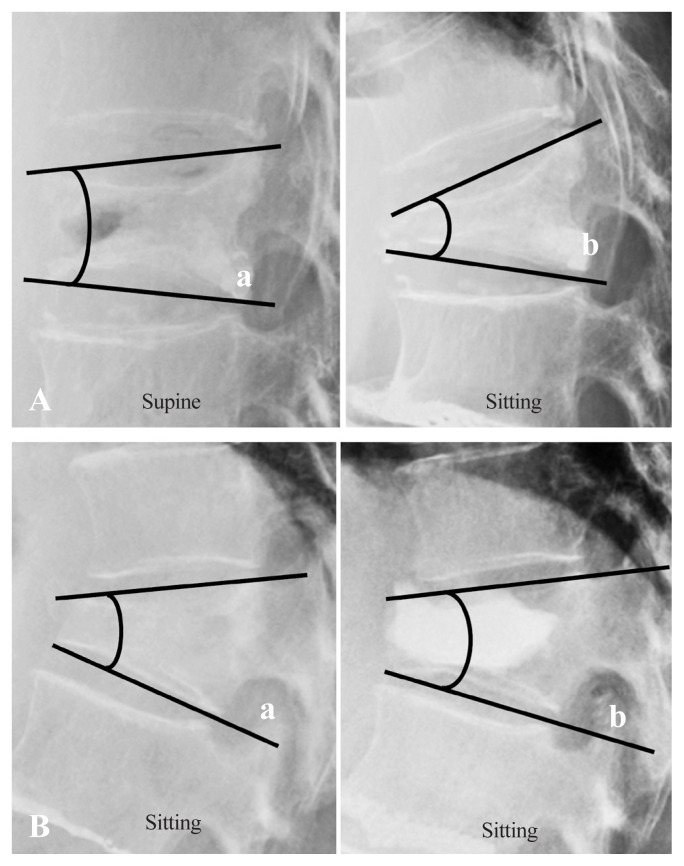

Methods: We retrospectively analyzed 189 patients who underwent BKP between 2012 and 2023, excluding those with pathological fractures. The incidence of AVF was assessed at 3 months after BKP. Risk factors, including age, sex, fracture site, prior vertebral fractures, bone mineral density, kyphosis angle, endplate damage, signal changes in the fractured vertebral body on magnetic resonance imaging, vertebral instability, and timing of BKP, were evaluated.